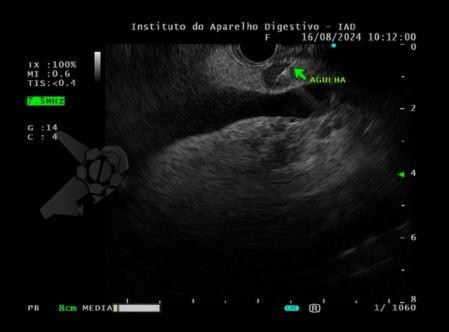

Foram realizadas punções ecoguiadas para obtenção de material para análise anatomopatológica (Foto 4).